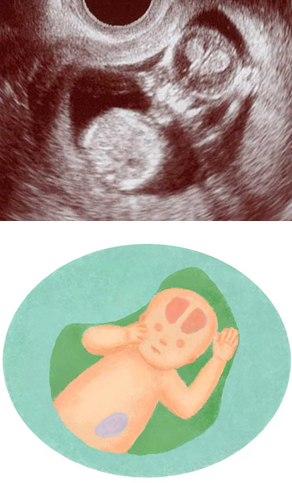

妊娠12週ころの超音波写真

骨が成長してきて白くはっきりと見えるようになります

骨の成長がさらに進みます。写真では鼻の骨が白く、目は黒く写ります。頭の中が左右にわかれているのが鮮明に。器官が完成されてくると、1週間ごとの違いは少なくなります。